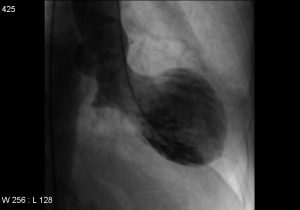

”Det første, vi som læger gør, er at undersøge hjertets kranspulsårer for at se, om der sidder en blodprop i hjertets blodkar – det vil der ikke gøre hos en patient med Broken Heart Syndrome. Dernæst foretager vi en ultralydsscanning for at få en fornemmelse af, hvordan hjertet pumper, og her vil man se, at hjertemusklen trækker sig sammen på en speciel måde. Forestil dig, at spidsen og den midterste del af hjertets for- og bagvæg ikke trækker sig sammen. Hjertet er med andre ord helt slapt nedadtil og pumper normalt opadtil.”

Sagt med andre ord pumper hjertet ikke, som det skal, og det er ikke bare noget, der kan mærkes, det er sådan set også noget, der kan ses. Thomas Emil Christensen beskriver, at hjertet får form som en vase, simpelthen fordi dele af hjertet holder op med at slå, og at dets venstre hovedkammer svulmer op.